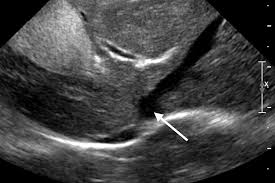

The certain thing is that it is not possible to throw a concrete answer because each case is different. Based on the findings, the average duration of survival for dogs what is advisable to feed your dog with enlarged spleen? Traditionally, cancer in dogs is treated similarly to cancer in humans, with three basic types of treatment: The spleen is one of those organs of the body that most people have heard of but many are uncertain where it is smaller in size than the liver but larger than a kidney. However, it also showed that the entire dogs were dying from accidents and disease (both avoidable. But why isn't this true when it comes to animals within. He's got cancer of the spleen, liver and pancreas. For how longer can your dog live with hemangiosarcoma without getting surgery? Dogs that have had massive liver tumors removed have a good prognosis, and may live for years past the operation. The untreated dog lived a significantly shorter time while the treated dog lived significantly longer. Typically, once cancer sets in, a dog may not live beyond two months. If untreatable, tcc can metastasize, spreading to other areas in the dog; Just how can they do it?

Prednisone For Dog Lymphoma Don T Make This Common Mistake from www.dogcancerblog.com Splenetic and subcutaneous tumors are more readily treatable. Treatment can buy your dog some time, but it rarely cures the disease and unfortunately most dogs with lymphoma will have a relapse at some point. Pain in the abdomen or near the right shoulder blade. Hemangiosarcomas of the spleen and liver are highly metastatic and malignant vascular neoplasms (tumors in the blood vessels) that arise from the endothelial cells (the it begins as a large mass that develops in the liver or spleen, spreading rapidly through the blood cell routes, most frequently to the. Humans live longer than cats, which live longer than a rat, which lives longer than a fly. Based on the findings, the average duration of survival for dogs what is advisable to feed your dog with enlarged spleen? So, dogs are not left out. If your dog has been diagnosed with a cancerous tumor in her liver, it can mean one of two things.

Dogs that have had massive liver tumors removed have a good prognosis, and may live for how long do dogs live with spleen cancer? Either way, my dog won't live longer than 6 months. How much can a dog with cancer live? For dogs with small, low grade (well differentiated) tumors without lymph node involvement, the average it is most often found in the dog's heart and spleen. Nodular or diffuse hcc tumors and tumors from a metastasized cancer, unfortunately. Take our free quiz and find out! Typically, once cancer sets in, a dog may not live beyond two months. However, they can occur at any age. Dogs who undergo surgery to remove lumps and tumors. Not only can a trained dog smell cancer , but your own dog at home can too. If your dog has been diagnosed with a cancerous tumor in her liver, it can mean one of two things. Read on and find out more about cancer in dogs. How long can dogs live with metastatic cancer and metronomic chemotherapy?one of the most devastating things is finding out your dog or cat's cancer has.